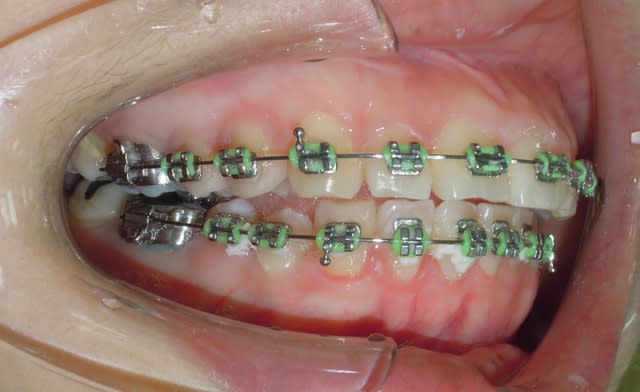

Quand soudain ..

Suite a un problème d'emplois du temps la patient n'a pas pus venir pendant deux mois, a sont retour nous avons la situation suivant .

- open bite

- over jet

La réponse n'est bien entendue pas que la patient fait son occlusion avec les 7 qui sont égressé (mais ça il faut examiner en bouche pour s'en apercevoir ).

Si on lui demande elle revient dans sa position d'occlusion habituelle (celle de début de traitement.)